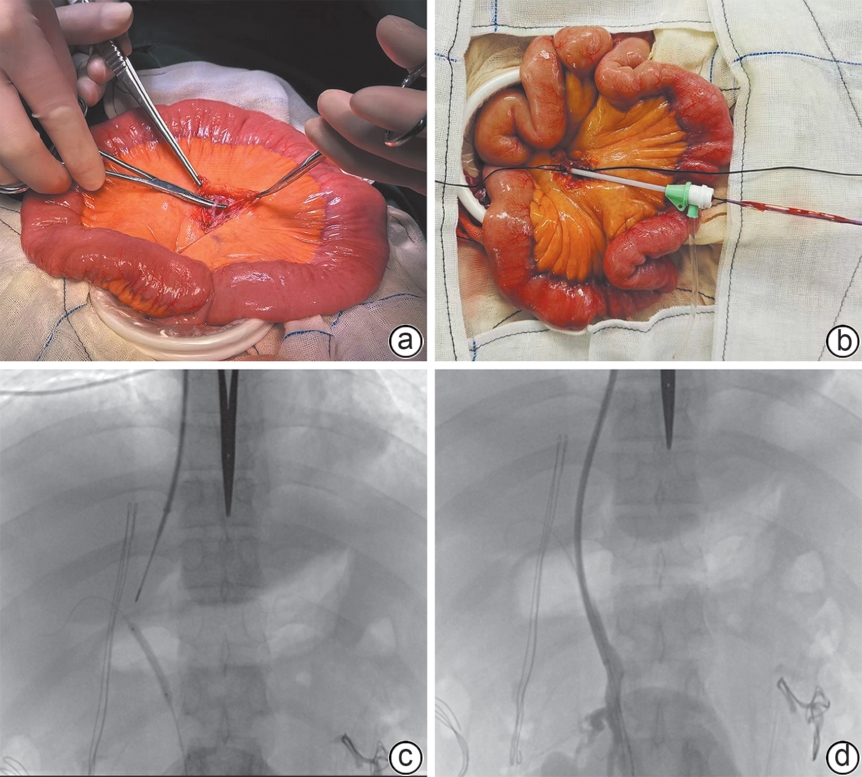

外科辅助经颈静脉肝内门体分流术治疗门静脉高压合并复杂门静脉血栓的效果及安全性分析

范振华, 董成宾, 李其美, 张裕, 吴一凡, 刘东方, 许光中, 王德仲, 陈建飞, 岳振东, 王磊

2026, 42(3): 586-592. DOI: 10.12449/JCH260313

摘要:

目的  探讨外科辅助经颈静脉肝内门体分流术(SA-TIPS)在门静脉高压合并复杂门静脉血栓(包括门静脉海绵样变)治疗中的可行性、安全性及疗效。  方法  选取2023年11月—2025年1月首都医科大学附属北京世纪坛医院收治的36例行SA-TIPS治疗的门静脉高压合并复杂门静脉血栓患者,统计并分析患者的一般情况、手术过程的技术资料(手术成功率、穿刺针数、手术时间、支架使用数量和分流道长度)、围手术期并发症及手术恢复情况等。比较分流术前后门静脉压力梯度(PPG)变化,计算PPG下降达标率和术后1周内支架通畅率。计量资料两组间比较采用配对样本t检验。  结果  36例患者中,34例(94.4%)成功实施SA-TIPS。围手术期并发症发生率为16.7%(6/36),包括胸腹腔出血3例,术中心律失常2例,切口感染1例。SA-TIPS分流后PPG较术前显著下降(t=19.85,P<0.01),其中PPG下降幅度≥50%的患者占76.5%(26/34),1周内影像学复查分流道通畅率为100%。  结论  SA-TIPS治疗合并复杂门静脉血栓(包括门静脉海绵样变)的门静脉高压具有技术成功率高、安全有效的优势,值得临床推广。